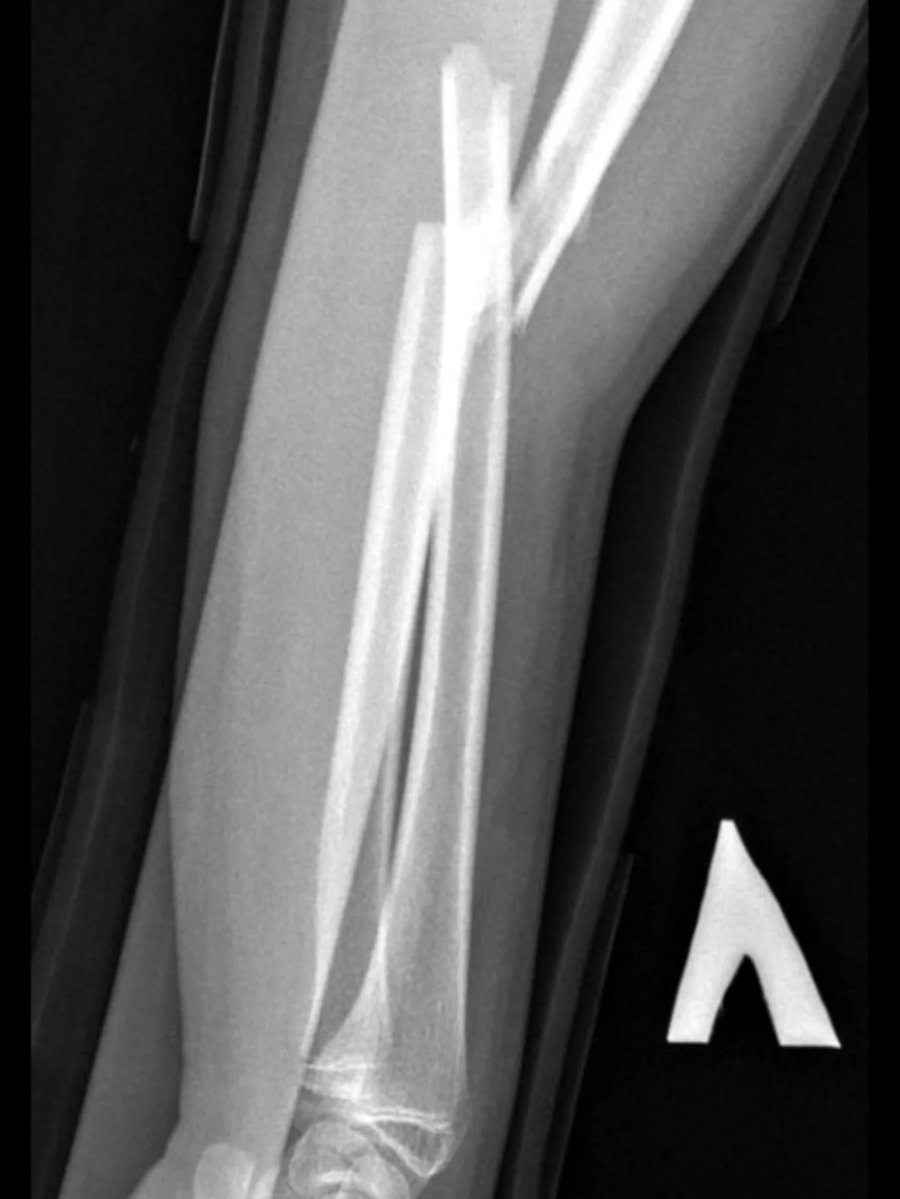

Ортопеди-травматологи Володимирського ТМО провели малоінвазивну операцію 14-річній дівчинці. Їй виконали закриту репозицію кісток лівого передпліччя з внутрішньокістковою фіксацією з ТЕНами.

Юній пацієнтці через два невеликі проколи шкіри передпліччя вправили зміщені уламки кістки без хірургічного розрізу, за допомогою спеціальних інструментів, відновлюючи правильне анатомічне положення кістки. Втручання проводилося під рентген-контролем.